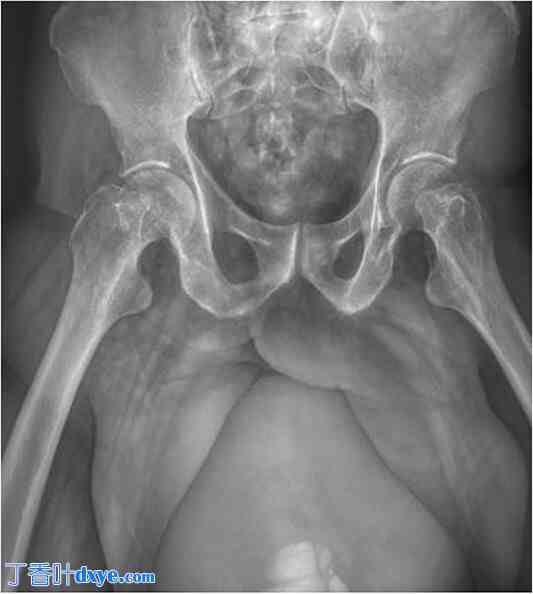

进行了影像学检查,包括一张简单的骨盆正位片,显示腹股沟区可见一处放射线不透光影像,向下延伸至尾侧,边界清晰规则 (图 2)。

图 2.

简单的骨盆正位片。